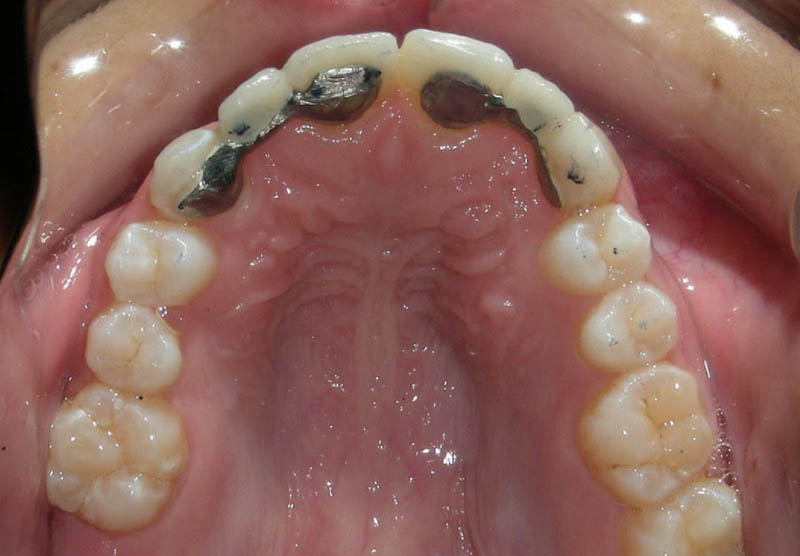

La momentul prezentării în clinică, în decembrie 2002, pacienta avea 8 ani şi o lună şi suferea de fibroză chistică şi de o deficienţă de dezvoltare a etajului mijlociu al feţei. Aceasta prezenta o anomalie de clasa I care mima o anomalie de clasa a III-a. Incisivii centrali, laterali şi caninii temporari maxilari, precum şi molarii prim şi secund de pe partea stângă erau în ocluzie inversă. În plus, pacienta prezenta coloraţii ale dinţilor de etiologie idiopatică (fig. 1). Autorii au considerat coloraţiile ca fiind de suprafaţă, extrinsece şi nu determinate de fibroza chistică, dovadă îndepărtarea acestora prin periaj profesional. Radiografia panoramică efectuată cu 6 luni înainte de prezentarea în clinica stomatologică relevă anodonţia incisivilor laterali superiori şi a premolarului secund drept inferior, ca şi posibila incluzie a caninilor maxilari, în special a celui stâng (fig. 2).